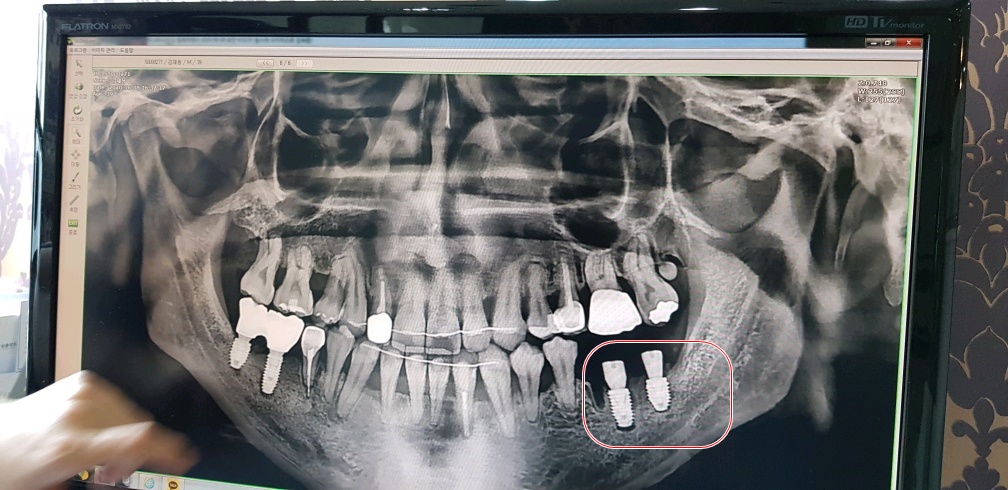

화면상에서 왼쪽치아 두개는 잘 됐다고 해서 다행인데

오른쪽 어금니 치아 두개다가 상태가 영...심각하다..

오른쪽 어금니가 저렇게 된 이유는 과거에(12년전 쯤) 사랑니가 어금니 옆쪽을 치고 나오면서

칫솔이 잘 닫지않는 맨구석이라 양치가 잘 안됐었고, 사랑니에 충치가 생기면서

멀쩡한 어금니 옆면까지 치고 나오면서 충치가 옮겨 붙었다.